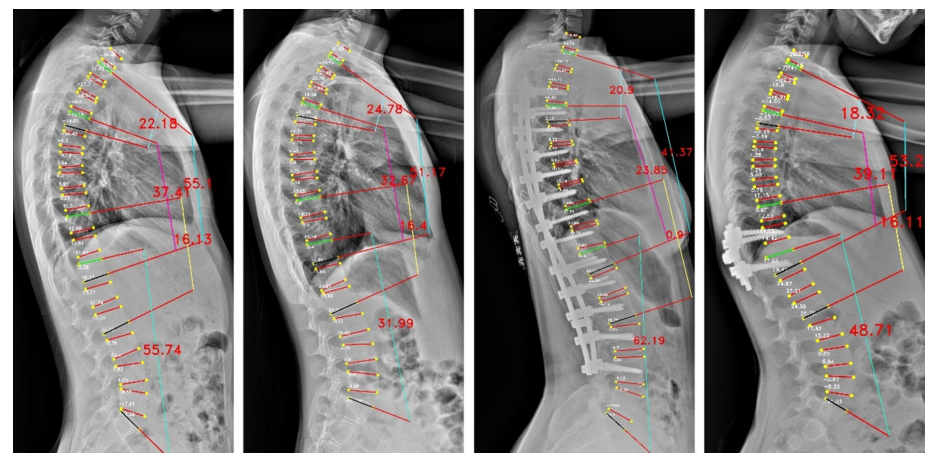

Cobb角是評估脊柱側彎程度的"金標準",其測量結果可以用於評估病情、制定治療計劃和跟蹤疾病進展。萬東Cobb角自動測量系統,1秒內即可完成Cobb角計算,較傳統手工測量(耗時>2 分鐘)效率提升百倍。經研究驗證,Cobb角平均測量誤差僅3.918°,ICC爲0.943,驗證了該算法技術指標頂尖、誤差小、重複性極好,相關論文收錄於脊柱外科和脊柱研究領域的國際頂級期刊之一《European Spine Journal》。

The Pearson correlation only on major Cobb angle of AP view images

The vertebrae four corner points and the Cobb angles measurement for AP view images

The vertebrae four corner points and the Cobb angles measurement for LAT view images

基於負重位CBCT的全脊柱三維Cobb角自動測量,實現了椎體的高精度自動分割,其Dice係數達0.9776(自動分割的結果越準確,Dice值就越接近1),誤差極小;三維Cobb角測量可接受度>97.05%,關鍵椎體識別準確率98.53%,顯著優於傳統方法。基於負重位CBCT椎體軸向旋轉角度自動測量,與人工測量一致性ICC 達0.76,誤差控制在±3.04° 內,實現了對椎體旋轉的客觀、高效、可重複測量,一鍵自動生成,高效助力臨牀精準診療。該研究入選中華醫學會放射學學術大會(CCR 2025)。